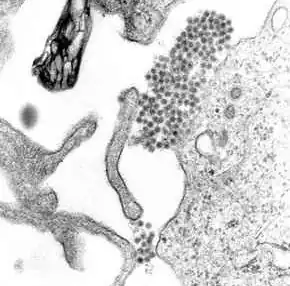

Dengue virus (DENV) is an RNA virus of the family Flaviviridae; genus Flavivirus. Other members of the same genus include yellow fever virus, West Nile virus, and Zika virus. Dengue virus genome (genetic material) contains about 11,000 nucleotide bases, which code for the three structural protein molecules (C, prM and E) that form the virus particle and seven other protein molecules that are required for replication of the virus.[29][30] There are four confirmed strains of the virus, called serotypes, referred to as DENV-1, DENV-2, DENV-3 and DENV-4. The distinctions between the serotypes are based on their antigenicity.[31]

For 2 to 10 days after becoming newly infected, a person's bloodstream will contain a high level of virus particles (the viremic period). A female mosquito that takes a blood meal from the infected host then propagates the virus in the cells lining its gut.[39] Over the next few days, the virus spreads to other tissues including the mosquito's salivary glands and is released into its saliva. Next time the mosquito feeds, the infectious saliva will be injected into the bloodstream of its victim, thus spreading the disease.[40] The virus seems to have no detrimental effect on the mosquito, which remains infected for life.[20]